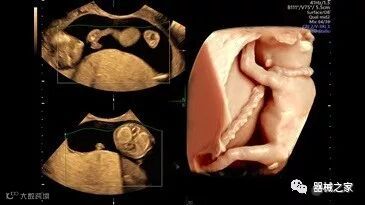

在RSNA 2018上发布的新成像被开发用于解决胎儿心脏和脑部成像问题。由于体积小且心率极快,因此难以进行详细的胎儿心脏评估。在18周时,胎儿的心脏大小与橄榄相当,每分钟跳动约150次。此外,结构本身非常复杂,婴儿不断运动,它始终是一个移动的目标。成像很重要,因为先天性心脏缺陷会影响全球每110个婴儿中的一个。

GE Healthcare用于胎儿超声的胎儿心脏和血管分析软件,在Voluson E10上提供,有助于在不到三分钟的时间内评估胎儿的心脏形状,大小和收缩性。称为辐射流的功能以三维视图显示血流。它还可以帮助显示缓慢流动的血液,例如神经血管循环。

Voluson E10

2018年发布的另一个例子是飞利浦的TrueVue,它提供照片般逼真的渲染,并能够在三维超声图像上改变光源的位置。它允许用户改变照明条件以提高对比度。可以移动光源以改变阴影并增加更多深度感知。还可以推动光源穿过组织以对解剖结构进行背光。